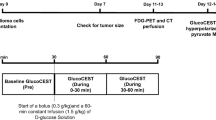

Radiation necrosis was initiated by employing a CT-guided 80-Gy single-dose irradiation of a half cerebrum in mice (n = 7). Intracerebral tumor was modeled with two orthotopic mouse models: GL261 glioma (n = 6) and Lewis lung carcinoma (LLC) metastasis (n = 7). 13C 3D MR spectroscopic imaging data were acquired following hyperpolarized [1-13C]pyruvate injection approximately 89 and 14 days after treatment for irradiated and tumor-bearing mice, respectively. The ratio of lactate to pyruvate (Lac/Pyr), normalized lactate, and pyruvate in contrast-enhancing lesion was compared between the radiation-induced necrosis and brain tumors. Histopathological analysis was performed from resected brains.